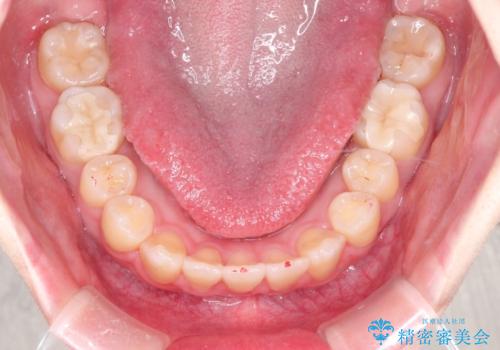

【インビザライン】歯を抜かずにできるだけ前歯を下げたい

- 前歯の前突を主訴に来院されました。

インビザライン を用いて、歯並びの改善を行うことができました。